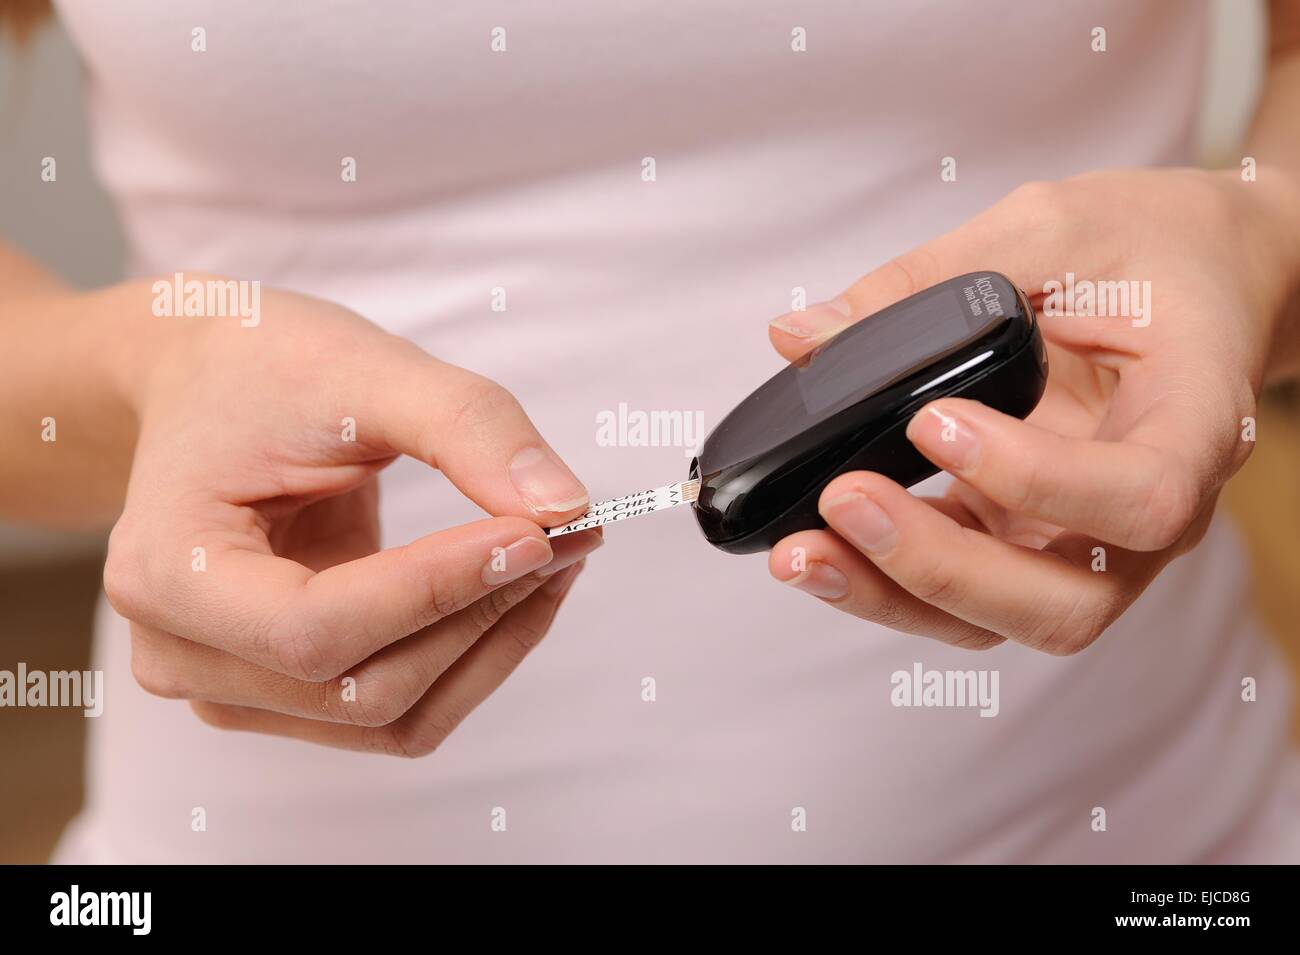

Accu chek avia nano Foto Stockhttps://www.alamy.it/image-license-details/?v=1https://www.alamy.it/foto-immagine-accu-chek-avia-nano-80179165.html

Accu chek avia nano Foto Stockhttps://www.alamy.it/image-license-details/?v=1https://www.alamy.it/foto-immagine-accu-chek-avia-nano-80179165.htmlRMEJCD9H–Accu chek avia nano

Accu chek avia nano Foto Stockhttps://www.alamy.it/image-license-details/?v=1https://www.alamy.it/foto-immagine-accu-chek-avia-nano-80179164.html

Accu chek avia nano Foto Stockhttps://www.alamy.it/image-license-details/?v=1https://www.alamy.it/foto-immagine-accu-chek-avia-nano-80179164.htmlRMEJCD9G–Accu chek avia nano

Accu chek avia nano Foto Stockhttps://www.alamy.it/image-license-details/?v=1https://www.alamy.it/foto-immagine-accu-chek-avia-nano-80179136.html

Accu chek avia nano Foto Stockhttps://www.alamy.it/image-license-details/?v=1https://www.alamy.it/foto-immagine-accu-chek-avia-nano-80179136.htmlRMEJCD8G–Accu chek avia nano

Accu chek avia nano Foto Stockhttps://www.alamy.it/image-license-details/?v=1https://www.alamy.it/foto-immagine-accu-chek-avia-nano-80179160.html

Accu chek avia nano Foto Stockhttps://www.alamy.it/image-license-details/?v=1https://www.alamy.it/foto-immagine-accu-chek-avia-nano-80179160.htmlRMEJCD9C–Accu chek avia nano

Accu chek avia nano Foto Stockhttps://www.alamy.it/image-license-details/?v=1https://www.alamy.it/foto-immagine-accu-chek-avia-nano-80179161.html

Accu chek avia nano Foto Stockhttps://www.alamy.it/image-license-details/?v=1https://www.alamy.it/foto-immagine-accu-chek-avia-nano-80179161.htmlRMEJCD9D–Accu chek avia nano

Accu chek avia nano Foto Stockhttps://www.alamy.it/image-license-details/?v=1https://www.alamy.it/foto-immagine-accu-chek-avia-nano-80179140.html

Accu chek avia nano Foto Stockhttps://www.alamy.it/image-license-details/?v=1https://www.alamy.it/foto-immagine-accu-chek-avia-nano-80179140.htmlRMEJCD8M–Accu chek avia nano

Accu chek avia nano Foto Stockhttps://www.alamy.it/image-license-details/?v=1https://www.alamy.it/foto-immagine-accu-chek-avia-nano-80179152.html

Accu chek avia nano Foto Stockhttps://www.alamy.it/image-license-details/?v=1https://www.alamy.it/foto-immagine-accu-chek-avia-nano-80179152.htmlRMEJCD94–Accu chek avia nano

Accu chek avia nano Foto Stockhttps://www.alamy.it/image-license-details/?v=1https://www.alamy.it/foto-immagine-accu-chek-avia-nano-80179149.html

Accu chek avia nano Foto Stockhttps://www.alamy.it/image-license-details/?v=1https://www.alamy.it/foto-immagine-accu-chek-avia-nano-80179149.htmlRMEJCD91–Accu chek avia nano